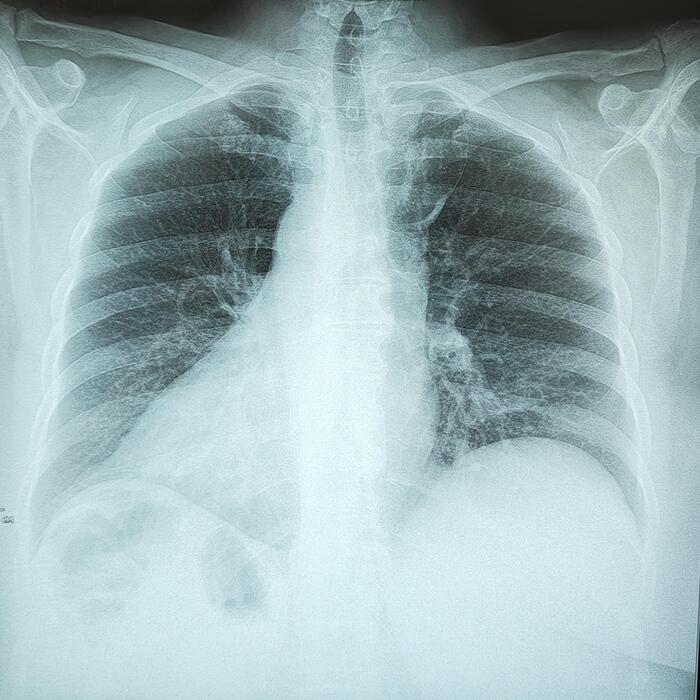

Справа по парастернальной линии, чаще на уровне 1-го межреберья (иногда на уровне хрящевой части 1 или 2-го ребер) определяется небольшая в форме вытянутой капли тень (от 0,3 до 0,8 мм ширины и от 0,6 до 2,5 мм длины) с четкими контурами. Эта «капля», заостряясь кверху, переходит в нежную (волосяную) линейную тень добавочной междолевой щели; она направлена кверху и дугообразно изгибается выпуклостью кнаружи.

Порок развития протекает бессимптомно. Его диагностируют на рентгенограммах, флюорограммах в прямой/задней проекциях.